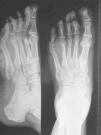

El motivo de la consulta fue tumoración y dolor en una determinada área anatómica, aunque con mayor frecuencia en extremidades inferiores. El tamaño de la tumoración en el momento de la consulta oscilaba entre 1 y 16cm (media de 6,7cm). Desde que aparecieron los síntomas, el retraso promedio en el diagnóstico fue de 17 meses, aunque en algún caso se llegó a los 2,5 años. El mayor retraso se correlacionó con un mayor tamaño del tumor y un estadio más avanzado. No obstante, cabe destacar que la paciente con el SS de localización cervical refería quejarse de dolor cervical desde hacía al menos 2 años, y el tamaño del tumor fue inferior al del paciente con SS de localización en mediopié. A todos los pacientes se les realizó radiología simple y resonancia magnética (RM). La radiología simple fue de ayuda diagnóstica en los casos con estadios avanzados. En el caso del varón con tumoración en el mediopié (estadio III ), la radiología simple mostró un aumento de partes blandas entre el cuarto y el quinto metatarsiano, y una rotura del hueso cortical del cuarto metatarsiano adyacente (figura 1). En el caso del SS en muslo (estadio IV ) se observó, además del aumento de partes blandas, un engrosamiento perióstico compatible con periostitis. La RM fue la técnica de elección, tanto para el diagnóstico como para decidir el abordaje quirúrgico de la lesión.

Figura 1. Radiografía simple de pie izquierdo en 2 proyecciones, que muestra un aumento de partes blandas entre el cuarto y el quinto metatarsiano y una rotura del hueso cortical del cuarto metatarsiano adyacente.